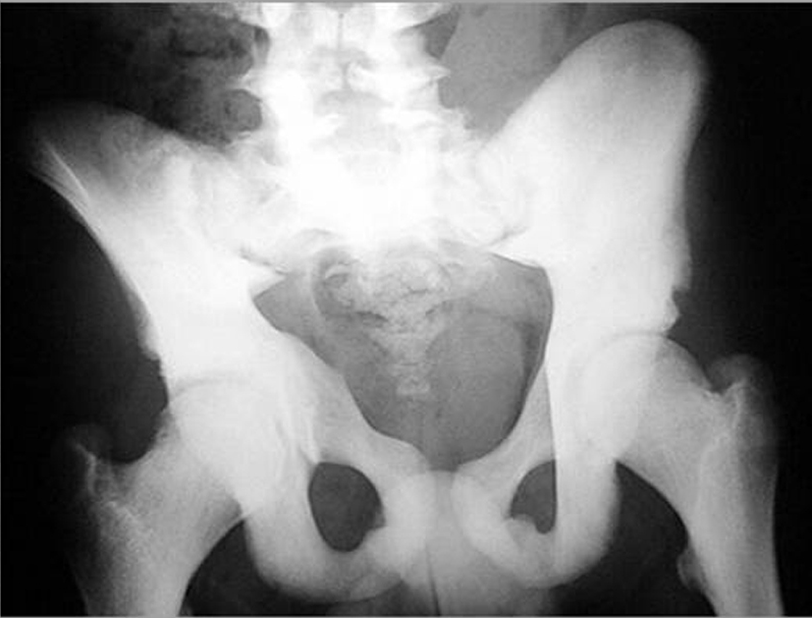

Osteopetrosis is an inherited connective tissue disease resulting in abnormally dense bones prone to fracture. Mutations in more than a dozen known genes result in dysfunctional osteoclasts and accumulation of old bone normally resorbed. In severe cases, malfunctioning endochondral bone replaces the marrow space, resulting in inadequate hematopoiesis. Resultant pancytopenia can lead to opportunistic infection and death in childhood. Compensatory hepatosplenomegaly ensues as a result of extramedullary hematopoiesis. Cranial nerve deficits can manifest, as attempted blood cell production in concert with ongoing hypertrophy enlarges bony structures of the skull. The continued production of abnormal endochondral bone also results in brittleness predisposing to fracture, which occurs even in patients with less severe forms and normal life expectancy. đ¸Treatment: HLA-matched bone marrow transplant to repopulate functional osteclast progenitors.